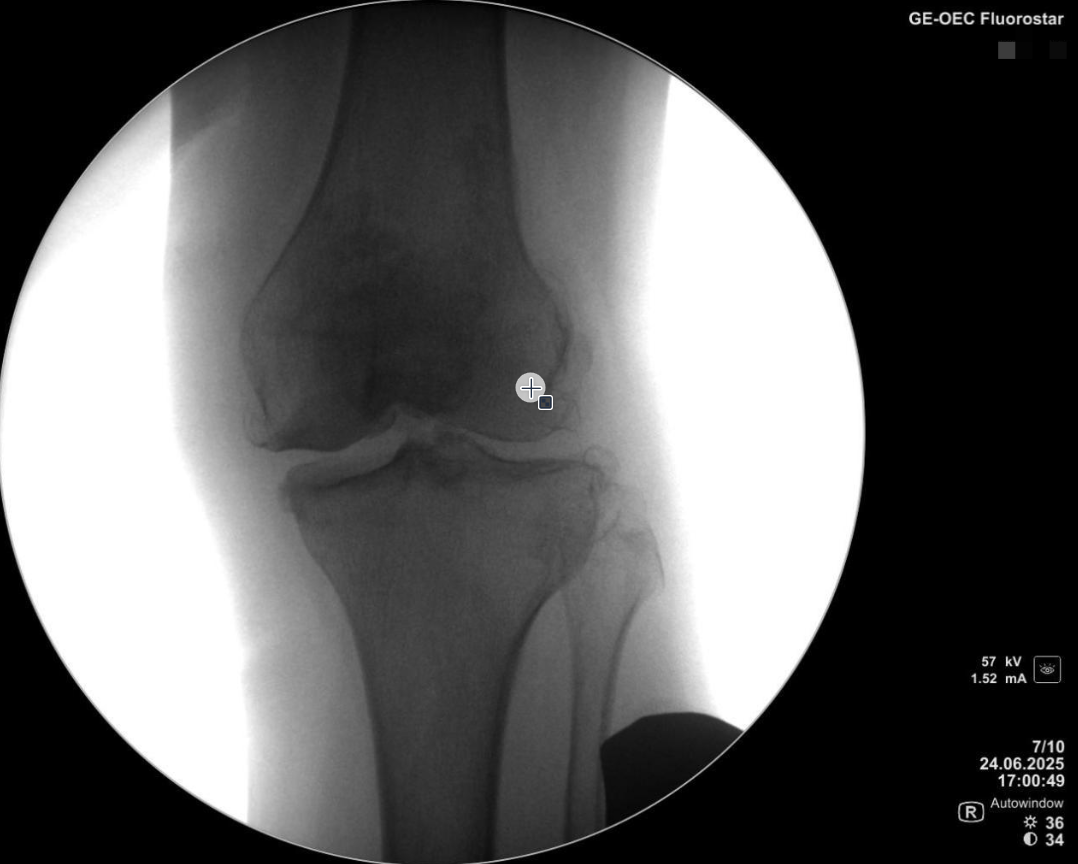

术前透视片

外翻应力位